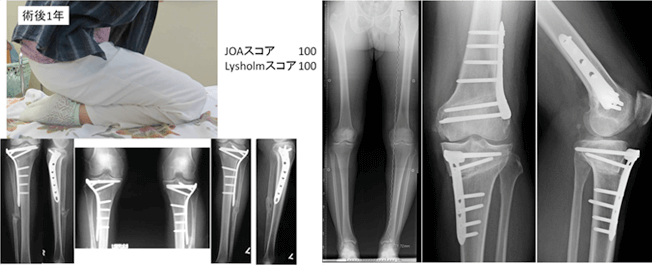

我々は、軟骨機能を温存するため、inside-out法による強固な縫合を、関節鏡を用いて行っております。より強固に縫合するため特殊な縫合方法で行っております。下肢アライメント不良がある膝に対しては、アライメント矯正手術を併用した半月板縫合術も行う場合もあります。

我々は、変形性膝関節症に対して関節温存手術を検討する場合、患者さんの下肢アライメント解析を行い、それぞれの変形に応じて種々の骨切り術(open wedge 型高位脛骨骨切り術、closed wedge 型高位脛骨骨切り術、大腿骨遠位骨切り術、脛骨顆外反骨切り術)を駆使し、治療にあたっております。関節鏡も併用し、骨髄刺激法や半月板縫合など、適宜処置を追加します。

硝子軟骨による軟骨再生は、整形外科医にとっても夢の治療であった。それが、2015年より保険収載され、臨床の現場で使用できるようになった。適応は4cm2以上の軟骨損傷で、1回目の手術で、膝の非荷重部の関節軟骨から関節鏡を用いて採取し、28日後に2回目の手術を行い、出来てきた培養軟骨を移植するものである。アライメント異常がある場合は、骨切り術なども併用することもある。